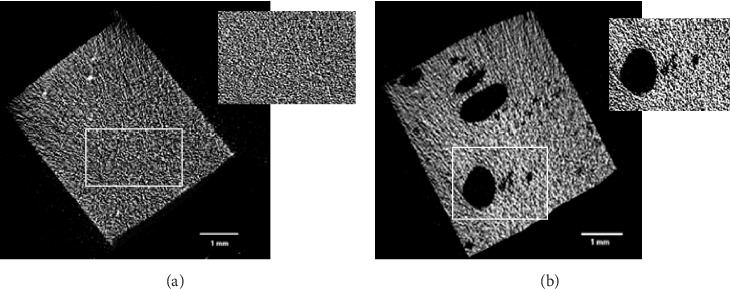

Aim: This study aimed to evaluate and compare the average pores size and closed porosity levels in different types of resin composites using micro-computed tomography (micro-CT). Materials and methods: Ninety specimens (2.5 mm × 4 mm × 4 mm) were prepared using 15 different materials divided into 15 groups (n = 6/group). Groups were either conventional packable (Filtek Universal Restorative and G-aenial A'chord), conventional flowable (CLEARFIL MAJESTY ES Flow, G-aenial Flo X, and G-aenial Universal Injectable), bulk fill flowable (SDR flow+ and Filtek Bulk Fill Flowable Restorative), dual-cure (Gradia Core and CLEARFIL DC Core Plus), or fiber-reinforced composites (Nova Pro Flow, Fibrafill DENTIN, everX Flow with either Dentin or Bulk shade, and everX Posterior), in addition to one glass hybrid material (EQUIA Forte HT Fil). All specimens were scanned using a micro-CT machine (Bruker Skyscan 1272), and analyzed for the average size, volume percentage, and distribution of closed porosities. Data was analyzed using Shapiro-Wilk for normality, followed by two-way ANOVA with Tukey's HSD for group comparisons. Pearson correlation assessed the relation between the average size and the percentage of closed pores. Results: The results revealed significant differences in closed porosity levels among the tested groups. Filtek Universal Restorative exhibited the lowest porosity (0.049%), while Fibrafill DENTIN had the highest (4.78%) and the largest average pore size (0.996 mm³). In contrast, A'chord had the smallest average closed pore size (0.017 mm³) (p  < 0.05). When the composites were categorized into flowable and packable variants, a significant difference (p  < 0.05) was observed in the average percentage of closed pores, with flowable composites showing a lower porosity (0.31%) compared to packable composites (1.25%). Conclusion: The findings highlight the influence of material type on porosity formation, with larger pore sizes correlating with higher closed porosity percentages.